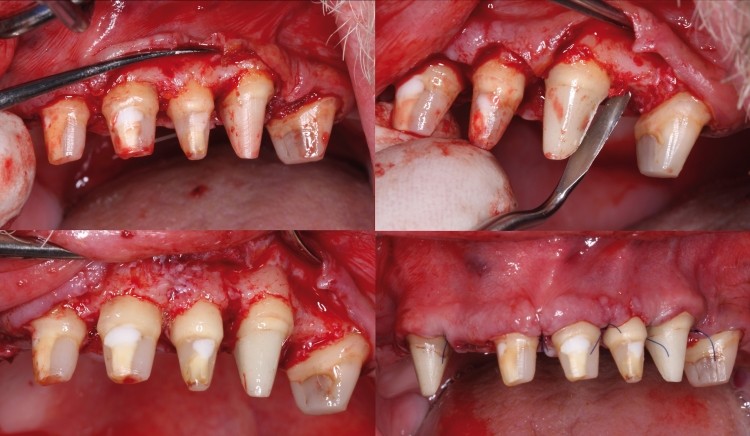

Bundan başqa, travma, ciddi karioz zədələnmə, normadan artıq preparasiya (diş yonulması) və s. nəticəsində diş tacının böyük ölçüdə dağılması zamanı bu dişlərin üzərinə qapaq, körpü konstruksiyalarının hazırlanması və ya bu dişlərin çıxan diş konstruksiyaları üçün (məsələn: teleskopprotezlər) fiksasiya elementi olaraq hazırlanması mümkün olmur. Buna səbəb diş toxumasının normadan artıq dağılmasıdır. Bu zaman tətbiq edilən metodlardan ən başlıcası diş tacının cərrahi uzadılmasıdır. Bu metodun tətbiqi ilə sümük müəyyən miqdarda uzaqlaşdırılaraq dişin tac hissesi uzadılmış olur. Nəticədə protetik olaraq yararsız diş yararlı duruma gətirilir.